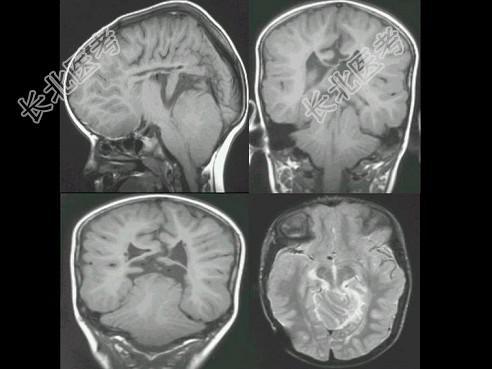

- 单项选择题男,3岁, 根据所示图像,最可能的诊断 ( )

A、脑室畸形

B、小脑畸形

C、脑干畸形

D、Chiari畸形

E、Dandy-Walker综合征